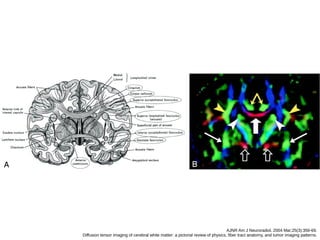

AJNR Am J Neuroradiol. 2004 Mar;25(3):356-69.

Diffusion tensor imaging of cerebral white matter: a pictorial review of physics, fiber tract anatomy, and tumor imaging patterns.

A, cíngulo

B, fascículo occipitofrontal inferior e longitudinal inferior.